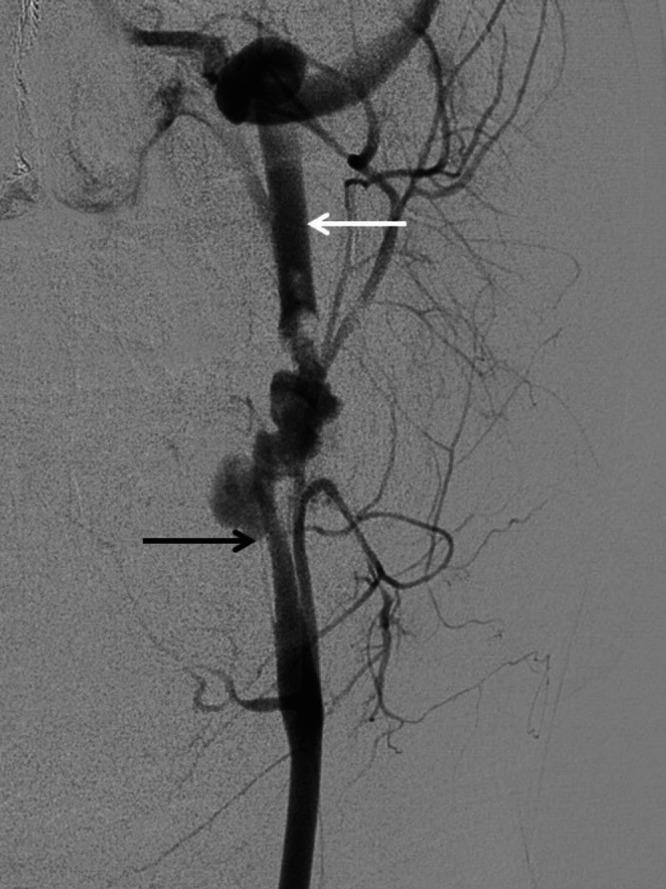

The occlusion was treated with flossing technique via the posterior communicating artery. After successful recanalization from a retrograde approach, the carotid artery occlusion was treated with a covered stent.

The flossing technique is well established in peripheral vascular disease and may be beneficial in certain cases in the neck vasculature when antegrade access is difficult to obtain. Recanalization of an occluded carotid artery from retrograde approach may be successful in cases of trauma from knife wounds.